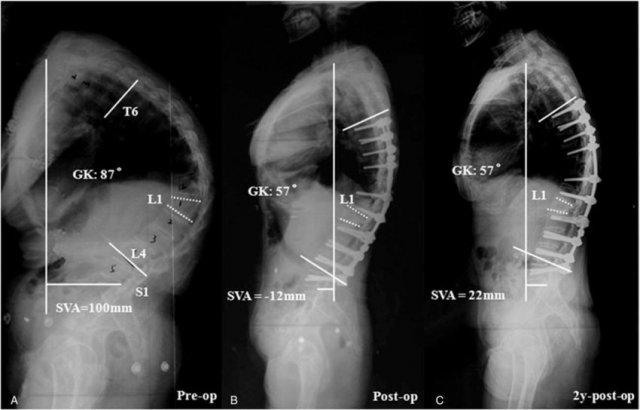

Ankylosing spondylitis (AS) with fibrothorax From pulmmed.blogspot.com

Source: pulmmed.blogspot.com